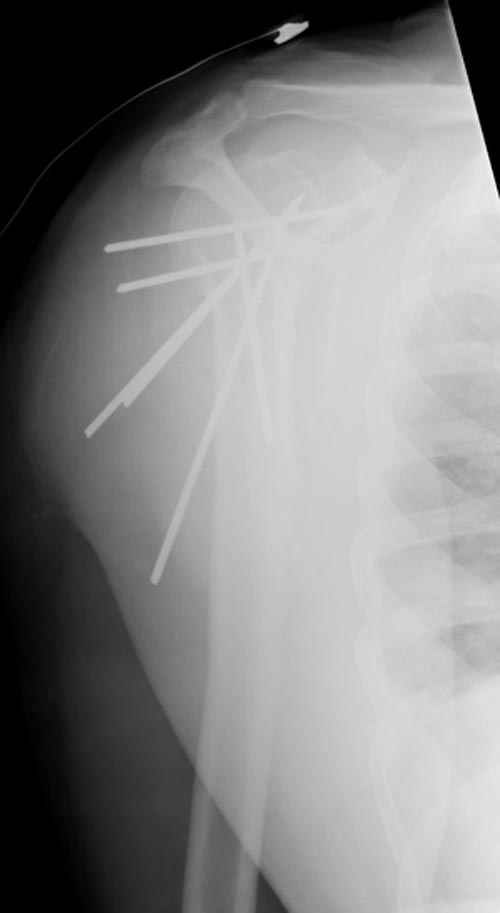

Сегодня взял больного повторно в операционную, не скажу, что повторная репозиция через неделю после первой попытки, была простая.

После удаления спиц попытался манипулировать отломками, но безуспешно, поэтому пришлось пользоваться периостальным элеватором, чтобы устранить смещение отломков и перепровести спицы. Проверил и перепроверил стабильность фиксации под ЭОПом, завтра Рг- будет готов, вот и поглядим....

Посылаю послеоперационные Рг граммы.

Всего Доброго,

Поздравляю, получилось просто замечательно. Если можно, расскажи чуть подробнее, как делали - как вправляли, как вводили спицы, поворачивали ли их?

Спасибо за поздравления:-))

Я и сам доволен результатом. В предпоследнем письме я кратко описал ход операции - закрыто репонировать не удалось( 2 недели с момента травмы и 1 неделя после неудачной репозиции) после удаления пучков спиц, пришлось сделать - 2см разрез на уровне перелома и с помощью периостального элеватора (золотое правило механики) *одеть* головку на дистальный отломок.

Спицы проводил через старые отверстия, вращая пучок импактором- направителем при его введении в головку.